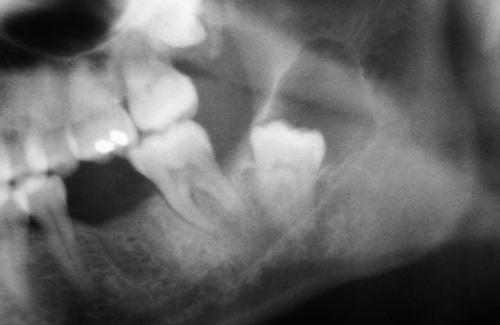

Radiographic Features

- well-defined radiolucent area

- large lesions may appear multilocular

- smooth and often corticated margins

- growth in an anteroposterior direction

- may involve an unerupted tooth (25% to 40%)

This large, multilocular cyst involves most of the ascending ramus and is growing in an anteroposterior direction.

odontogenic keratocyst (OKC)

This cyst involves the crown of an unerupted premolar, which appears similar to a dentigerous cyst.